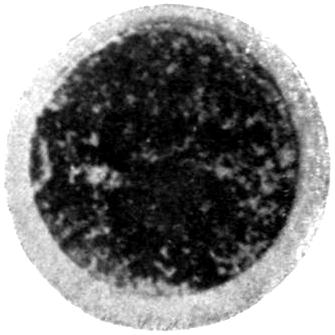

Plate II. 93

[43]

REFERENCES.

[1] Cloetta: Dixon Mann’s Forensic Medicine and Toxicology, p. 463.

[2] Oliver, Sir T.: Diseases of Occupation, p. 142.

[3] Goadby, K. W.: Departmental Committee on Lead Poisoning, etc., in China and Earthenware Manufacture, Appendix No. XXV.

[4] Meillère and Richer: Meillère’s Le Saturnisme. Paris, 1903.

[5] Blyth: Abstract of Proc. Chem. Soc., 1887-88.